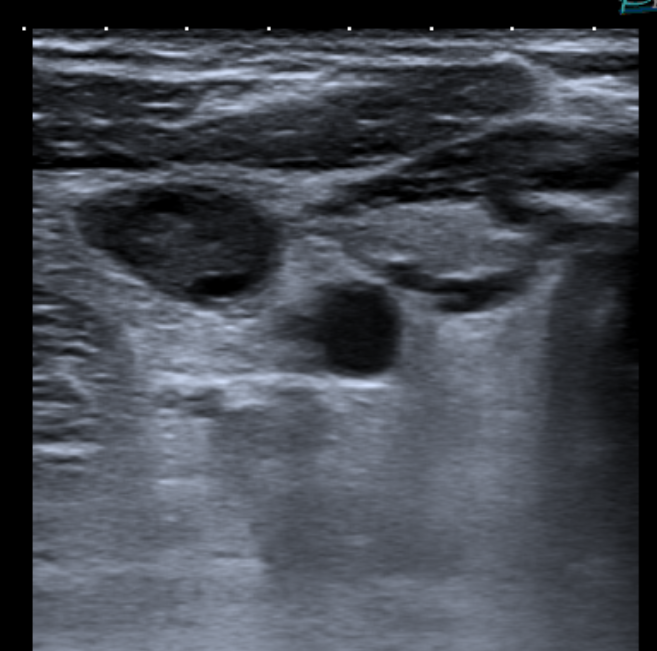

Thrombophilia studies revealed Hyperhomocysteinemia of 17.2 μmol/L (normal values 3.0 - 15.0), Total Protein S 54.1 % (normal values 65.0 - 140.0), and weak positiveness of a lupic anticoagulant. Six months after the episode, all parameters were normalized. Doppler ecography was done, in which an incidental jugular vein thrombosis was discovered (Figure 3 & 4).

Figure 3 Doppler December 2018: Incidental right jugular vein thrombosis.

Figure 4 Right sublcavia, left yugular and left subclavia veins were permeable.